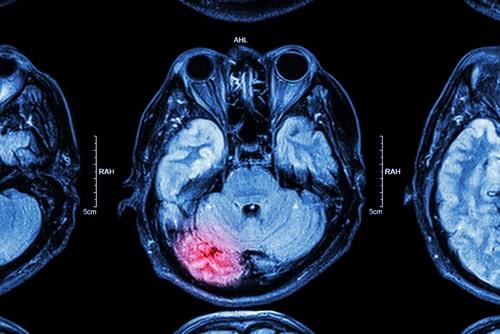

A traumatic brain injury or TBI is caused by an external force or trauma. A strong impact on the head during a car accident can damage brain tissue which can lead to temporary or permanent problems. Sometimes, the effects of a brain injury do not manifest themselves until weeks or months later. However, someone may feel there is something wrong if they experience chronic headaches, sleeping problems, memory loss, and sensitivity to lights and sounds. Depending on the severity of the initial impact, a person could appear to be fine but have a delayed trauma in which the brain becomes swollen.